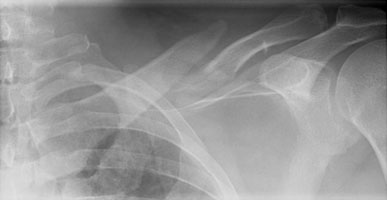

- Click on the image for a larger versionBAP radiograph of the left clavicle. This particular fracture has not healed, indicating nonunion.